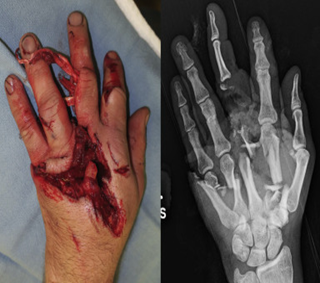

Hand Surgery

• Hand trauma

Examples: Syndactyly, Polydactyly, Hand trauma, Post-burn contracture

Hand Surgery Hand Surgery